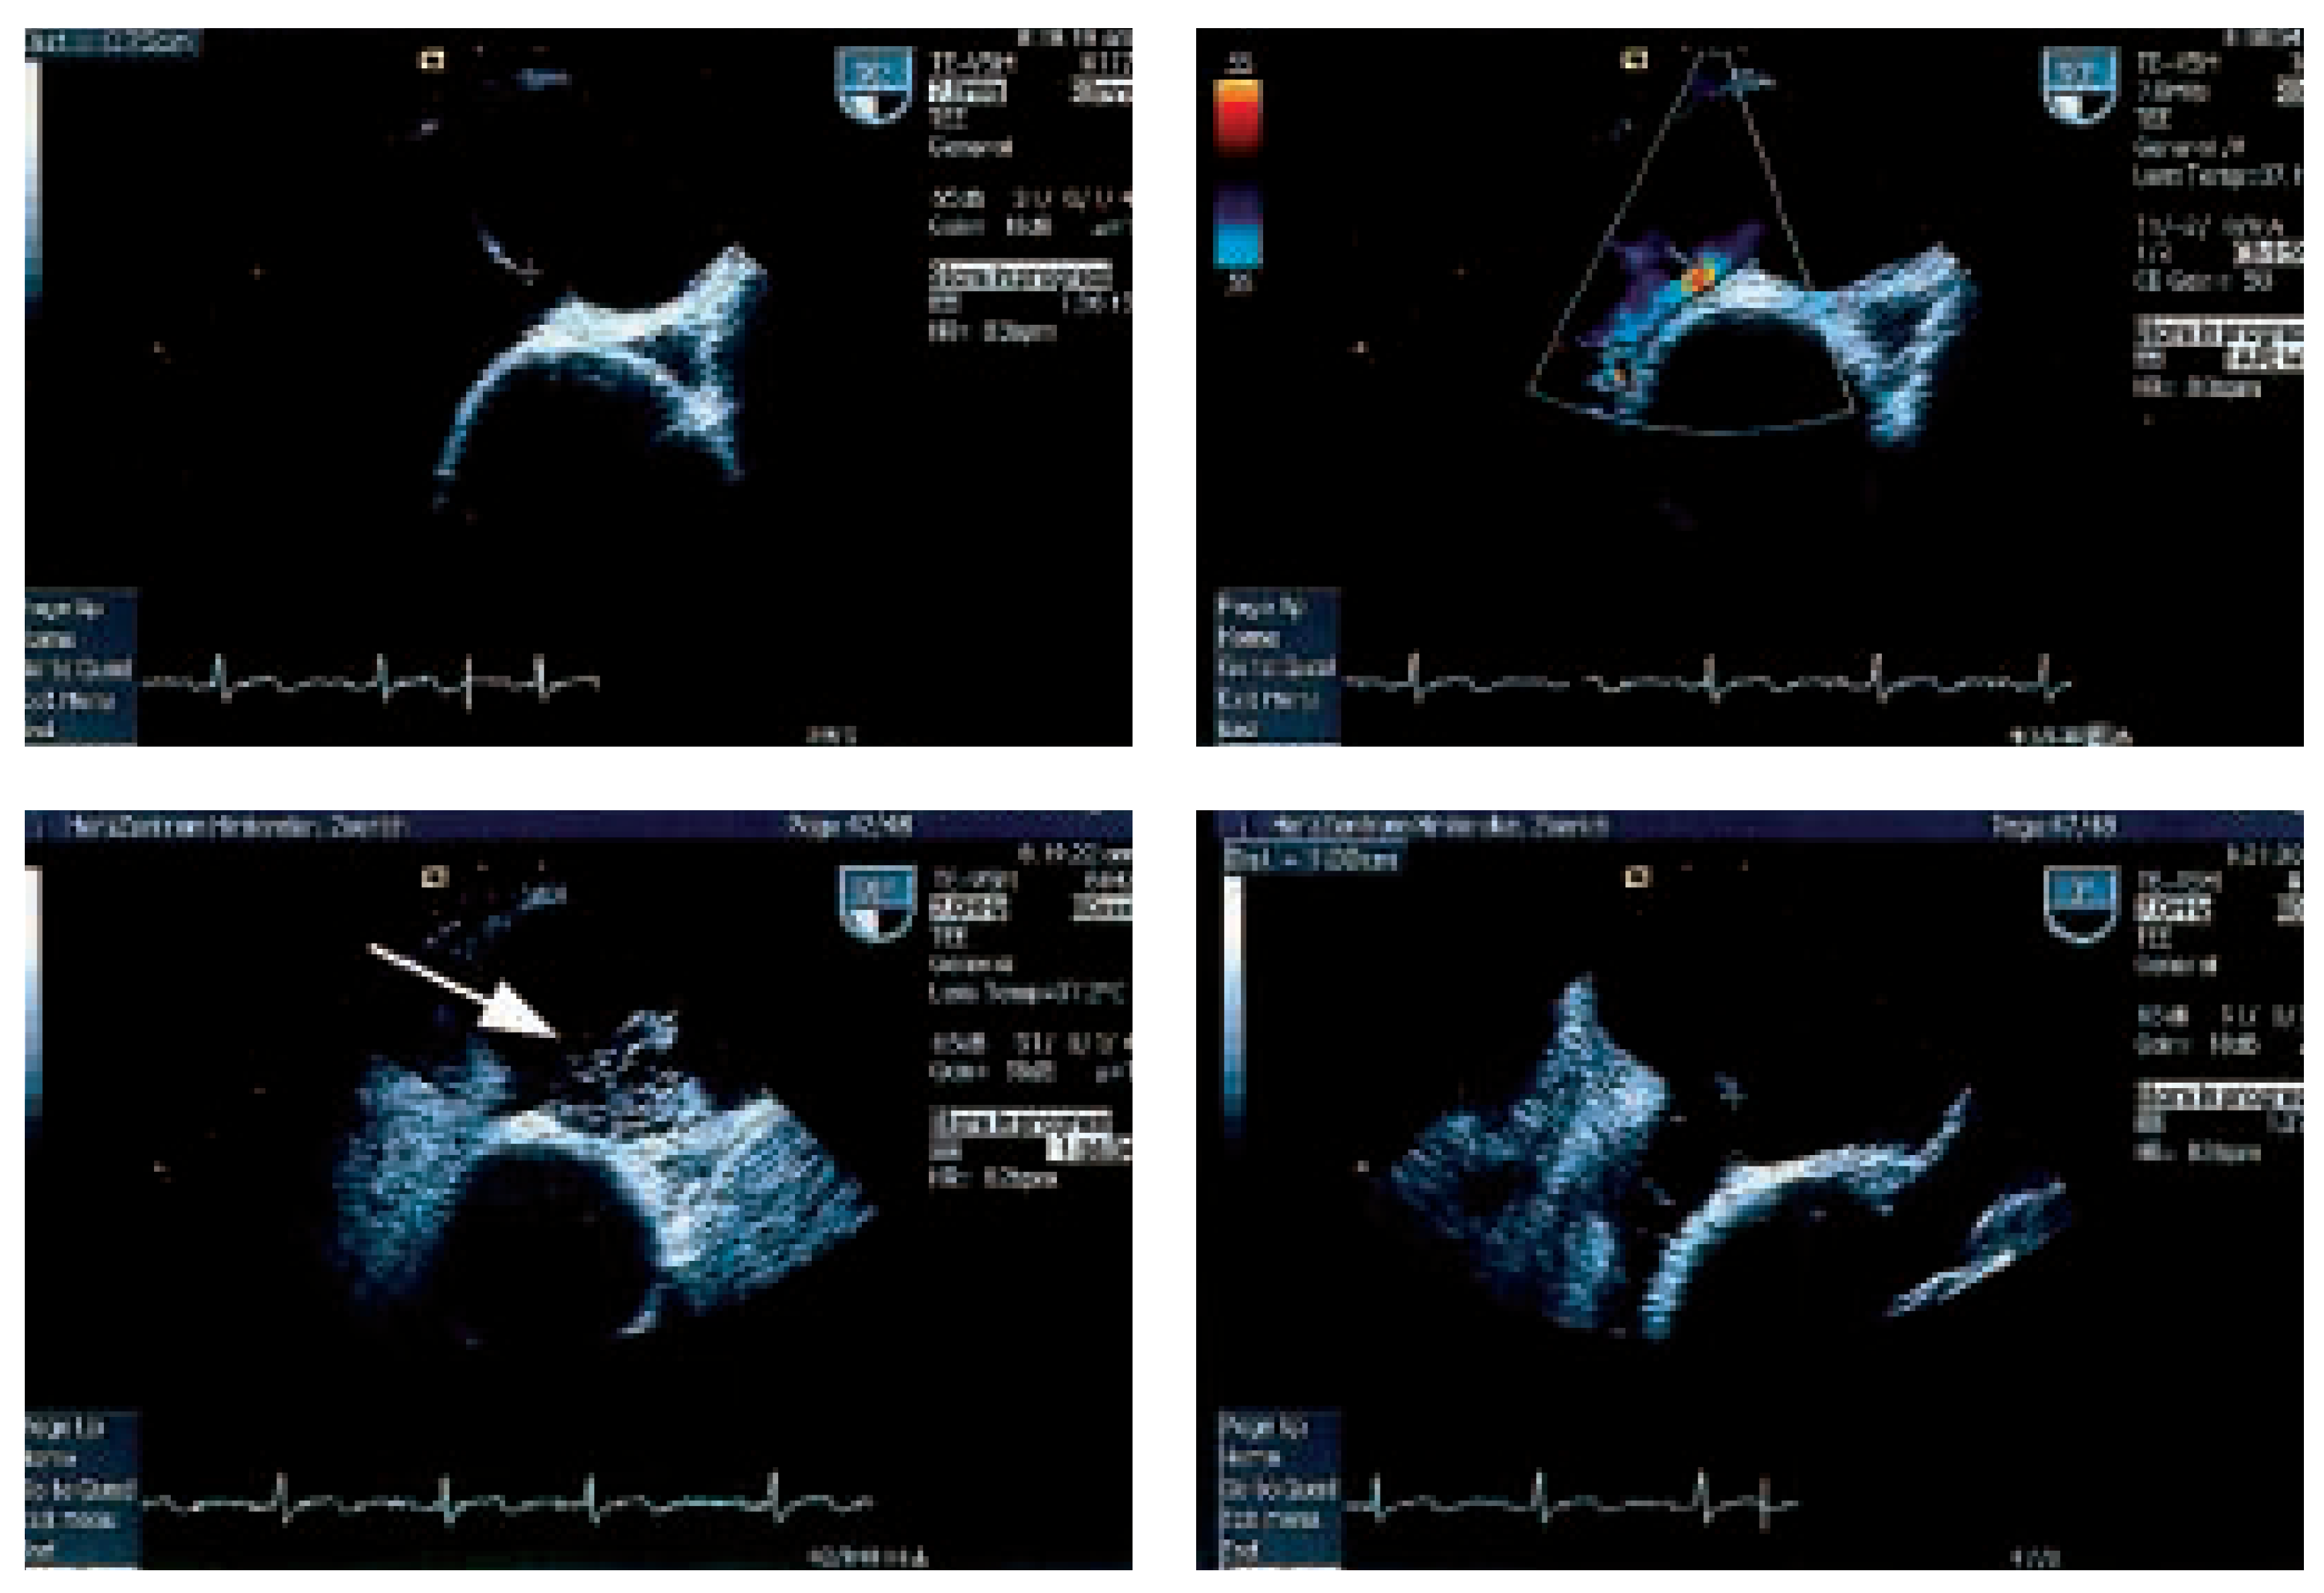

In der transthorakalen Echokardiographie fand sich eine linksventrikuläre Hypertrophie bei normaler systolischer Funktion. Zusätzlich bestand eine minime Mitralinsuffizienz und Aorteninsuffizienz. Es fand sich ein Vorhofseptumaneurysma mit einem kleinen Shunt auf Vorhofebene (Figure 1). Der pulmonal-arterielle Druck war entsprechend dem Doppler-echokardiographisch erhobenen Druckgradienten zwischen rechtem Ventrikel und rechtem Vorhof (30 mm Hg) nicht erhöht. In der anschliessenden transösophagealen Echokardiographie (Figure 2) konnte ein ASD Typ II im Bereich des Foramen ovale mit einem bidirektionalen Shunt, einem Vorhofseptumaneurysma und einer persistierenden Eustach-Klappe dargestellt werden.

Figure 2.

TEE-Untersuchung mit ASD II und Shunt im Farbdoppler und der Gabe von Bubbles mit Rechts-Links-Shunt unter Valsalva (Pfeil).